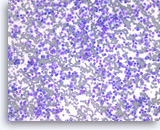

Small cell carcinoma,

Pancreas FNA, Direct Smear.

The aspirates show single and dyshesive clusters of malignant epithelial cells. The tumor cells are intermediate in size and have high nuclear to cytoplasmic ratios. Abundant necrosis is seen. Smear crush artifact (nuclear streaming) is focally seen.

40X

Small cell carcinoma,

Pancreas FNA, Direct Smear.

The aspirates show single and dyshesive clusters of malignant epithelial cells. The tumor cells are intermediate in size and have high nuclear to cytoplasmic ratios. Abundant necrosis is seen. Smear crush artifact (nuclear streaming) is focally seen.

40X

Small cell carcinoma,

Pancreas FNA, Direct Smear.

The tumor cells have speckled (“salt and pepper”) chromatin and inconspicuous nucleoli with some nuclear molding. Necrosis is readily seen. The features suggest a high grade small cell neuroendocrine carcinoma. Small cell carcinomas may be primary or metastatic to the pancreas and they may need to be distinguished from other “small blue cell tumors”. Immunohistochemical studies are useful to confirm neuroendocrine differentiation and to help exclude other forms of small blue cell tumors.

40X

Small cell carcinoma,

Pancreas FNA, Direct Smear.

The tumor cells have speckled (“salt and pepper”) chromatin and inconspicuous nucleoli with some nuclear molding. Necrosis is readily seen. The features suggest a high grade small cell neuroendocrine carcinoma. Small cell carcinomas may be primary or metastatic to the pancreas and they may need to be distinguished from other “small blue cell tumors”. Immunohistochemical studies are useful to confirm neuroendocrine differentiation and to help exclude other forms of small blue cell tumors.

40X

Small cell carcinoma,

Pancreas FNA, Cell Block.

The tumor cells with high nuclear to cytoplasmic ratios are present singly and in loose groups. Necrosis is present.

20X

Small cell carcinoma,

Pancreas FNA, Cell Block.

The tumor cells with high nuclear to cytoplasmic ratios are present singly and in loose groups. Necrosis is present.

20X

Small cell carcinoma,

Pancreas FNA, Cell Block.

The tumor cells are immunoreactive with neuroendocrine markers, chromogranin, synaptophysin or CD56. Shown is a synaptophysin stain, which is positive in tumor cells. It is important to note that small cell carcinomas of pancreatic origin may be positive for the pulmonary marker TTF-1. Clinical correlation is required to rule out a lung metastasis if TTF-1 is positive.

20X

Small cell carcinoma,

Pancreas FNA, Cell Block.

The tumor cells are immunoreactive with neuroendocrine markers, chromogranin, synaptophysin or CD56. Shown is a synaptophysin stain, which is positive in tumor cells. It is important to note that small cell carcinomas of pancreatic origin may be positive for the pulmonary marker TTF-1. Clinical correlation is required to rule out a lung metastasis if TTF-1 is positive.

20X